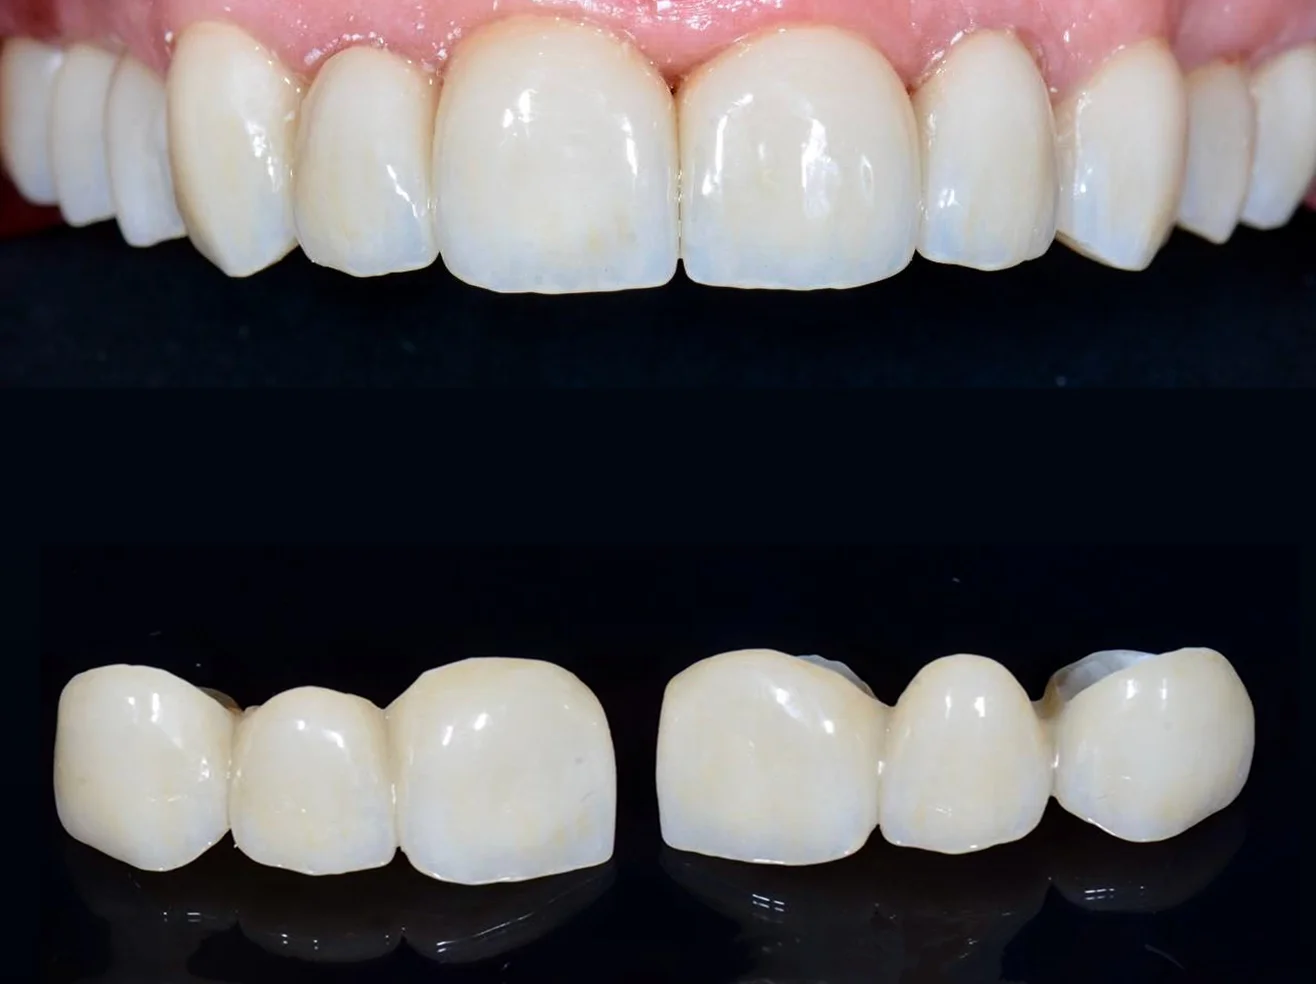

Відновлення функції жування після втрати зубів

Протезування проводиться з використанням цифрових технологій та з сучасних матеріалів (циркон).

ПРОТЕЗУВАННЯ НА ІМПЛАНТАХ

При відсутніх зубах проводимо заміщення дефектів за допомогою дентальних імплантів та протезуванням цирконієвими коронками.

06 Я хочу змінити форму та колір моїх зубів. Чи можливо це?

Так. Лікар проводить художню реставрацію зубів із застосуванням мікроскопа, цифрового прогнозування та сучасних пломбувальних матеріалів для досягнення естетичного результату.